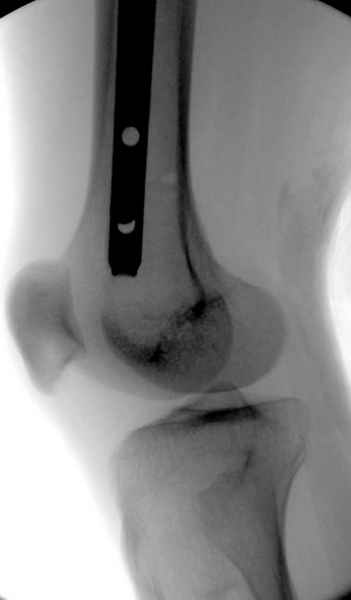

Второй случай тоже репозиция из малого доступа, больному 19 лет, множественные огнестрельные повреждениия конечностей, живота и черепа, правая конечность холодная, без пульсации. Ортопедический диагноз: огнестрельный перелом правого бедра. При срочной ангиографии повреждения сосудов не подтвердилось, конечность из-за ургентности состояния больного зафиксирована временным наружным фиксатором и больной оставлен на операционном столе для срочной лапаротомии хирургической службой.

Больной долго оставался нестабильным, только на 14 день удалось заменить на антеградный интромедуллярный штифт TFN (trochanteric femoral nail) SmithNephew. После неудачной попытки закрытой репозиции, несмотря на использование "joystick", проксимальный стержень от

наружного фиксатора, (перелом начал срастаться) репозицию провели из малого доступа, затем остальные этапы операции.

Случай был представлен из-за того, что больного оперировали после наружной фиксации и был риск инфекцирования через места проведения стержней (на снимках), прошло больше 3 месяцев, выписан из амбулаторной службы из-за отсутсвия надобности дальнейшего наблюдения.